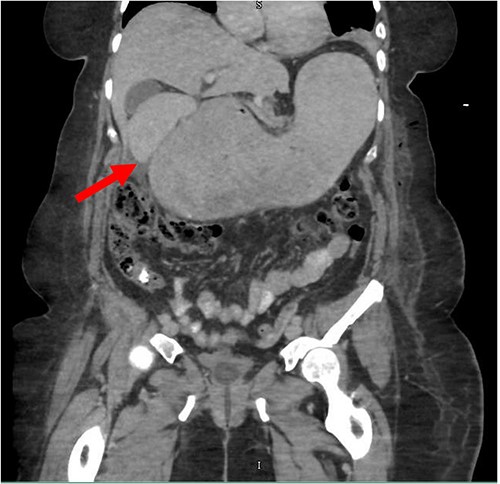

Despite the insertion of the NGT yielding 1500 cc output in 24 hours, the patient continued to experience severe abdominal pain. Urgent abdominal and pelvic computed tomography (CT) scans were taken, as seen in Figs 2–4. The CT scans showed gastric distension and the spleen positioned anteriorly in the right upper quadrant. Consequently, the decision was made to promptly bring the patient to the operating room for a diagnostic laparoscopy with plan to detorse the spleen.

CT of the abdomen and pelvis (coronal slice) showing gastric distention and the spleen positioned in the right upper quadrant.

Our patient’s pre-existing conditions presented challenges in distinguishing between expected postoperative discomfort and potential complications following her recent adrenalectomy. This uncertainty, combined with a normal WBC count, absence of fever, and regular bowel function, initially led the medical team to attribute her pain to the recent surgery two days prior, delaying her diagnosis and potentially exacerbating her condition. Subsequent imaging became imperative, revealing a persistent large gastric bubble despite NGT decompression, and malposition of the spleen (Fig. 3). This prompted immediate preoperative measures to facilitate a diagnostic laparoscopy.